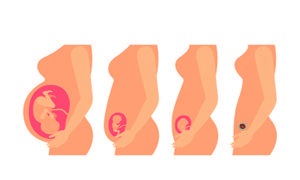

子宫是女性独特的生殖器官,不仅能够通过每个月子宫内膜规律性的脱落形成月经,稳定女性正常的新陈代谢,还有着孕育新生命的重要作用。下面就为大家来分析一下,子宫薄可以怀孕吗?